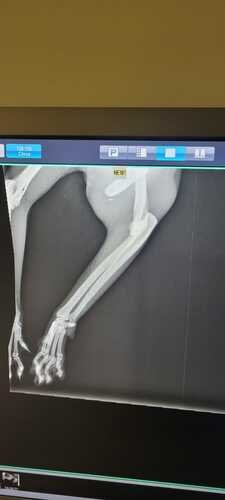

A Chica foi raptada de nossa casa, e quando a encontramos descobrimos que foi atropelada 2x. A sua patinha está quebrada e precisará ser amputada. Com o HVET da UnB conseguimos um bom desconto, carinho e atenção com a nossa Chiquinha.

(IMAGENS DA FRATURA)